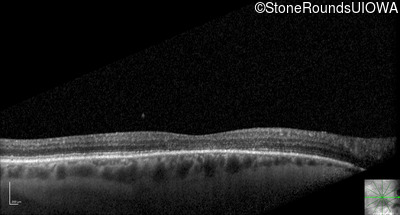

Optical Coherence Tomography - Right - 20/160 -2

Exemplar / OCT Stack